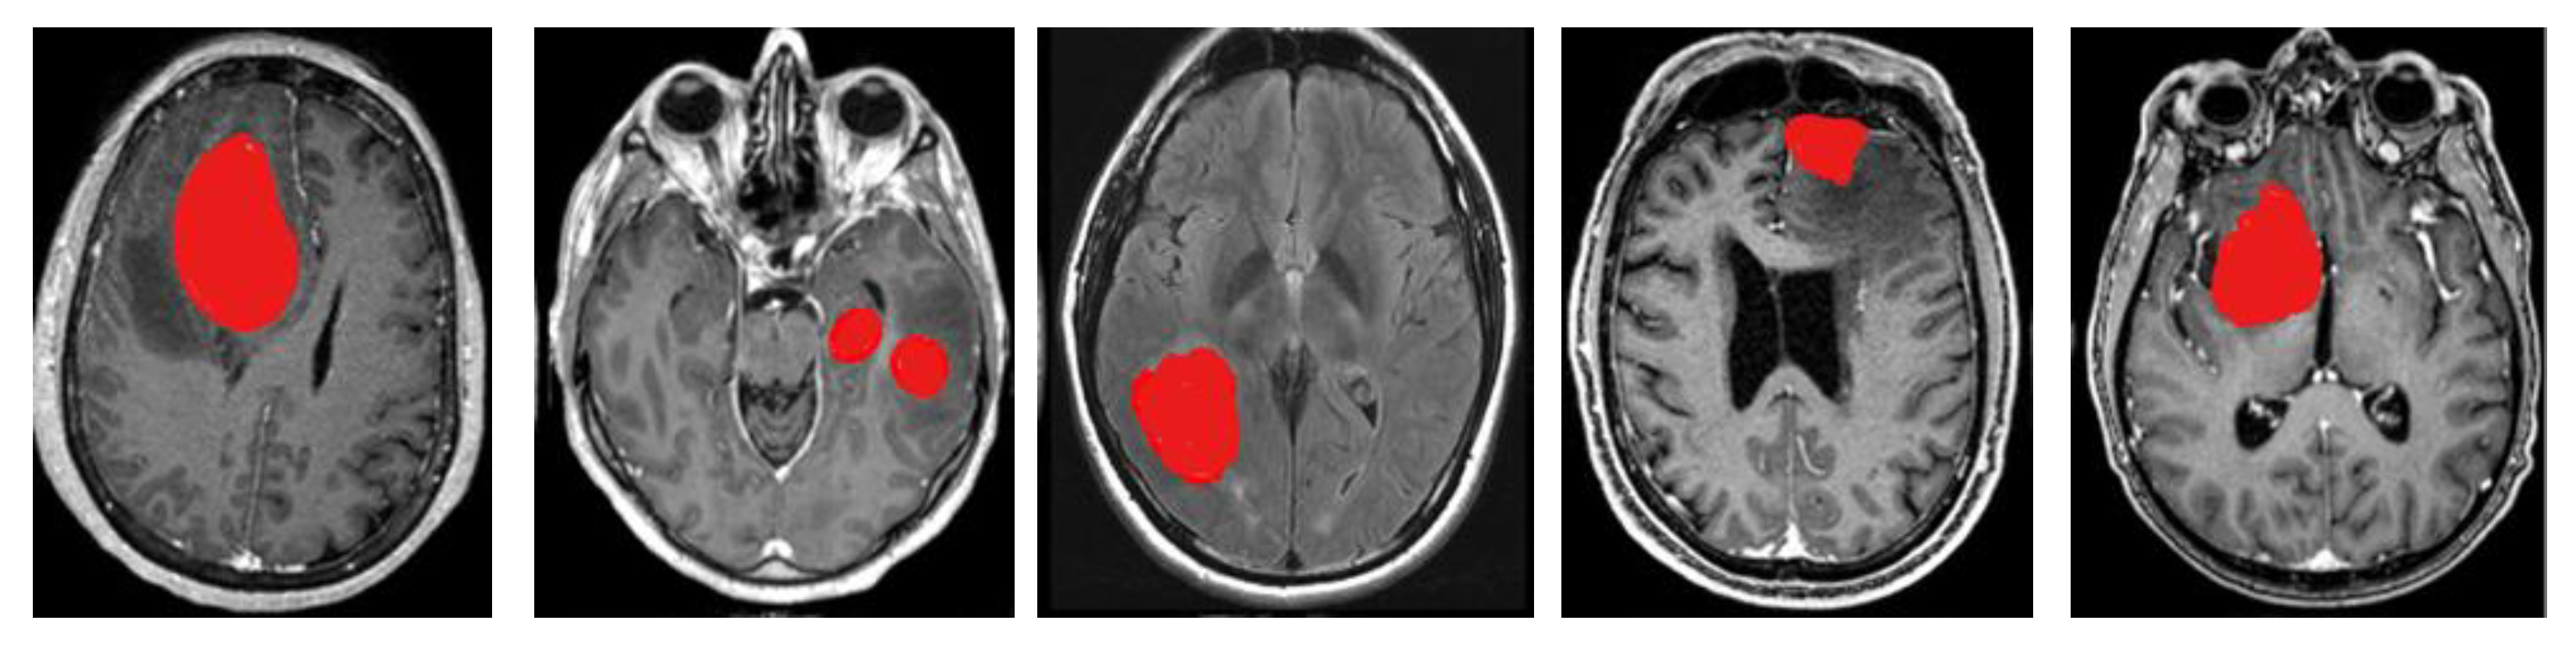

- Researchers have been able to recognize malignancies such as meningioma, glioma, and pituitary tumors using the newly developed deep learning network structure of ResNet-152 as a pre-trained model in the deep convolutional neural network.

4.2. Segmentation

5.1. Dataset Description